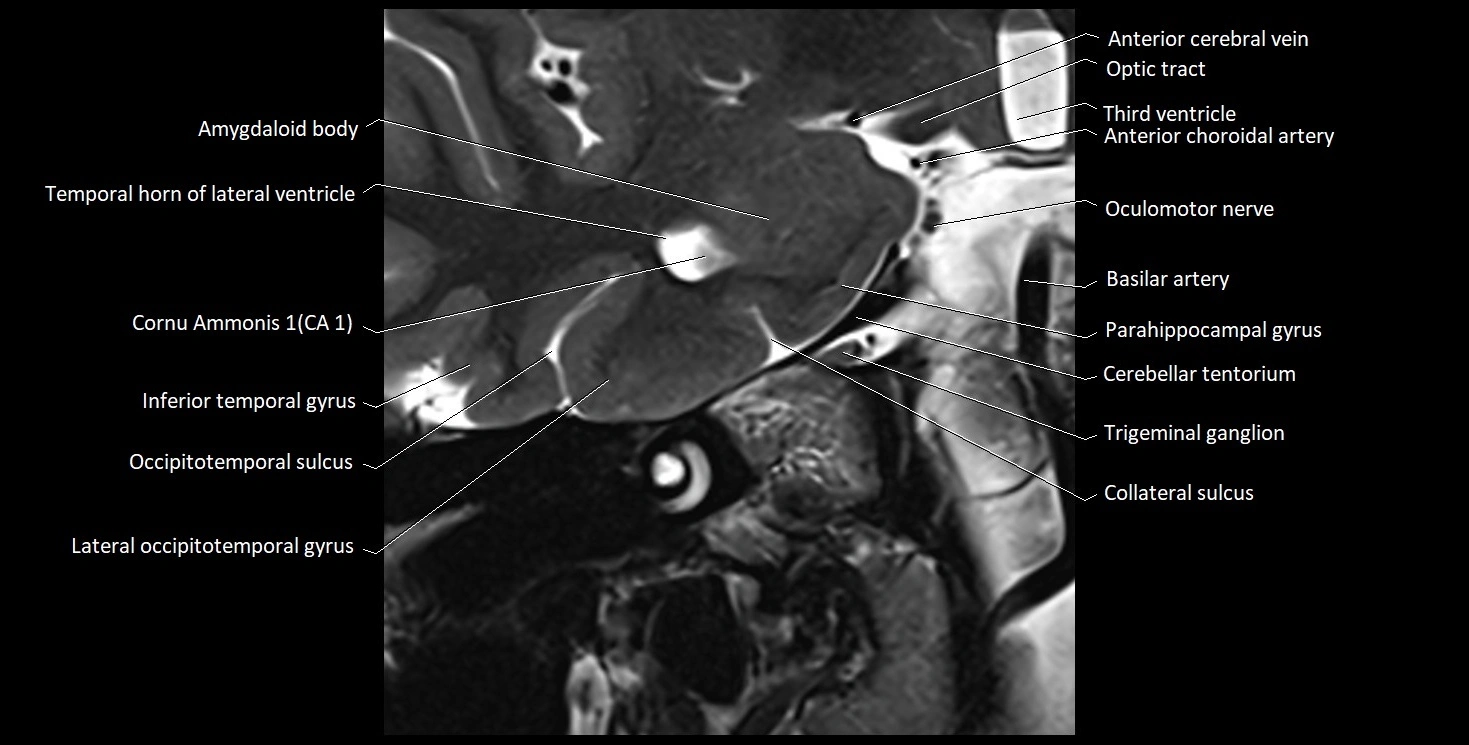

The alveus of the hippocampus is a thin, white matter layer covering the superior (ventricular) surface of the hippocampus within the temporal horn of the lateral ventricle. It consists of myelinated efferent fibers arising primarily from the pyramidal neurons of the hippocampus. These fibers converge medially to form the fimbria of the hippocampus, which continues posteriorly into the fornix, forming a crucial part of the Papez circuit involved in memory consolidation and emotional processing.

The alveus serves as the initial output pathway of the hippocampal formation, linking it to other limbic structures including the hypothalamus, mammillary bodies, and cingulate gyrus. Because of its intimate relationship with the hippocampal head and tail, it is often evaluated in cases of temporal lobe epilepsy, hippocampal sclerosis, and neurodegenerative diseases.

Location and Structure

• Position: Lies on the ventricular (superior) surface of the hippocampus, beneath the ependyma of the inferior horn of the lateral ventricle.

• Composition: A thin sheet of myelinated axons derived mainly from hippocampal pyramidal cells.

• Course: Fibers run medially along the hippocampal surface to form the fimbria of the hippocampus, which curves upward and backward into the fornix.

• Relations:

• Superiorly: Ependyma and CSF of the temporal horn of the lateral ventricle

• Inferiorly: Pyramidal cell layer of the hippocampus (CA1 region)

• Medially: Fimbria and fornix

• Laterally: Temporal lobe white matter and parahippocampal gyrus

MRI Appearance

T1-weighted images:

• Alveus: Thin linear high signal band (due to myelinated fibers) overlying the hippocampal gray matter.

• Hippocampal gray matter: Intermediate signal intensity.

• CSF of lateral ventricle: Dark (low signal).

T2-weighted images:

• Alveus: Low signal line overlying brighter hippocampal gray matter.

• CSF: Bright hyperintense.